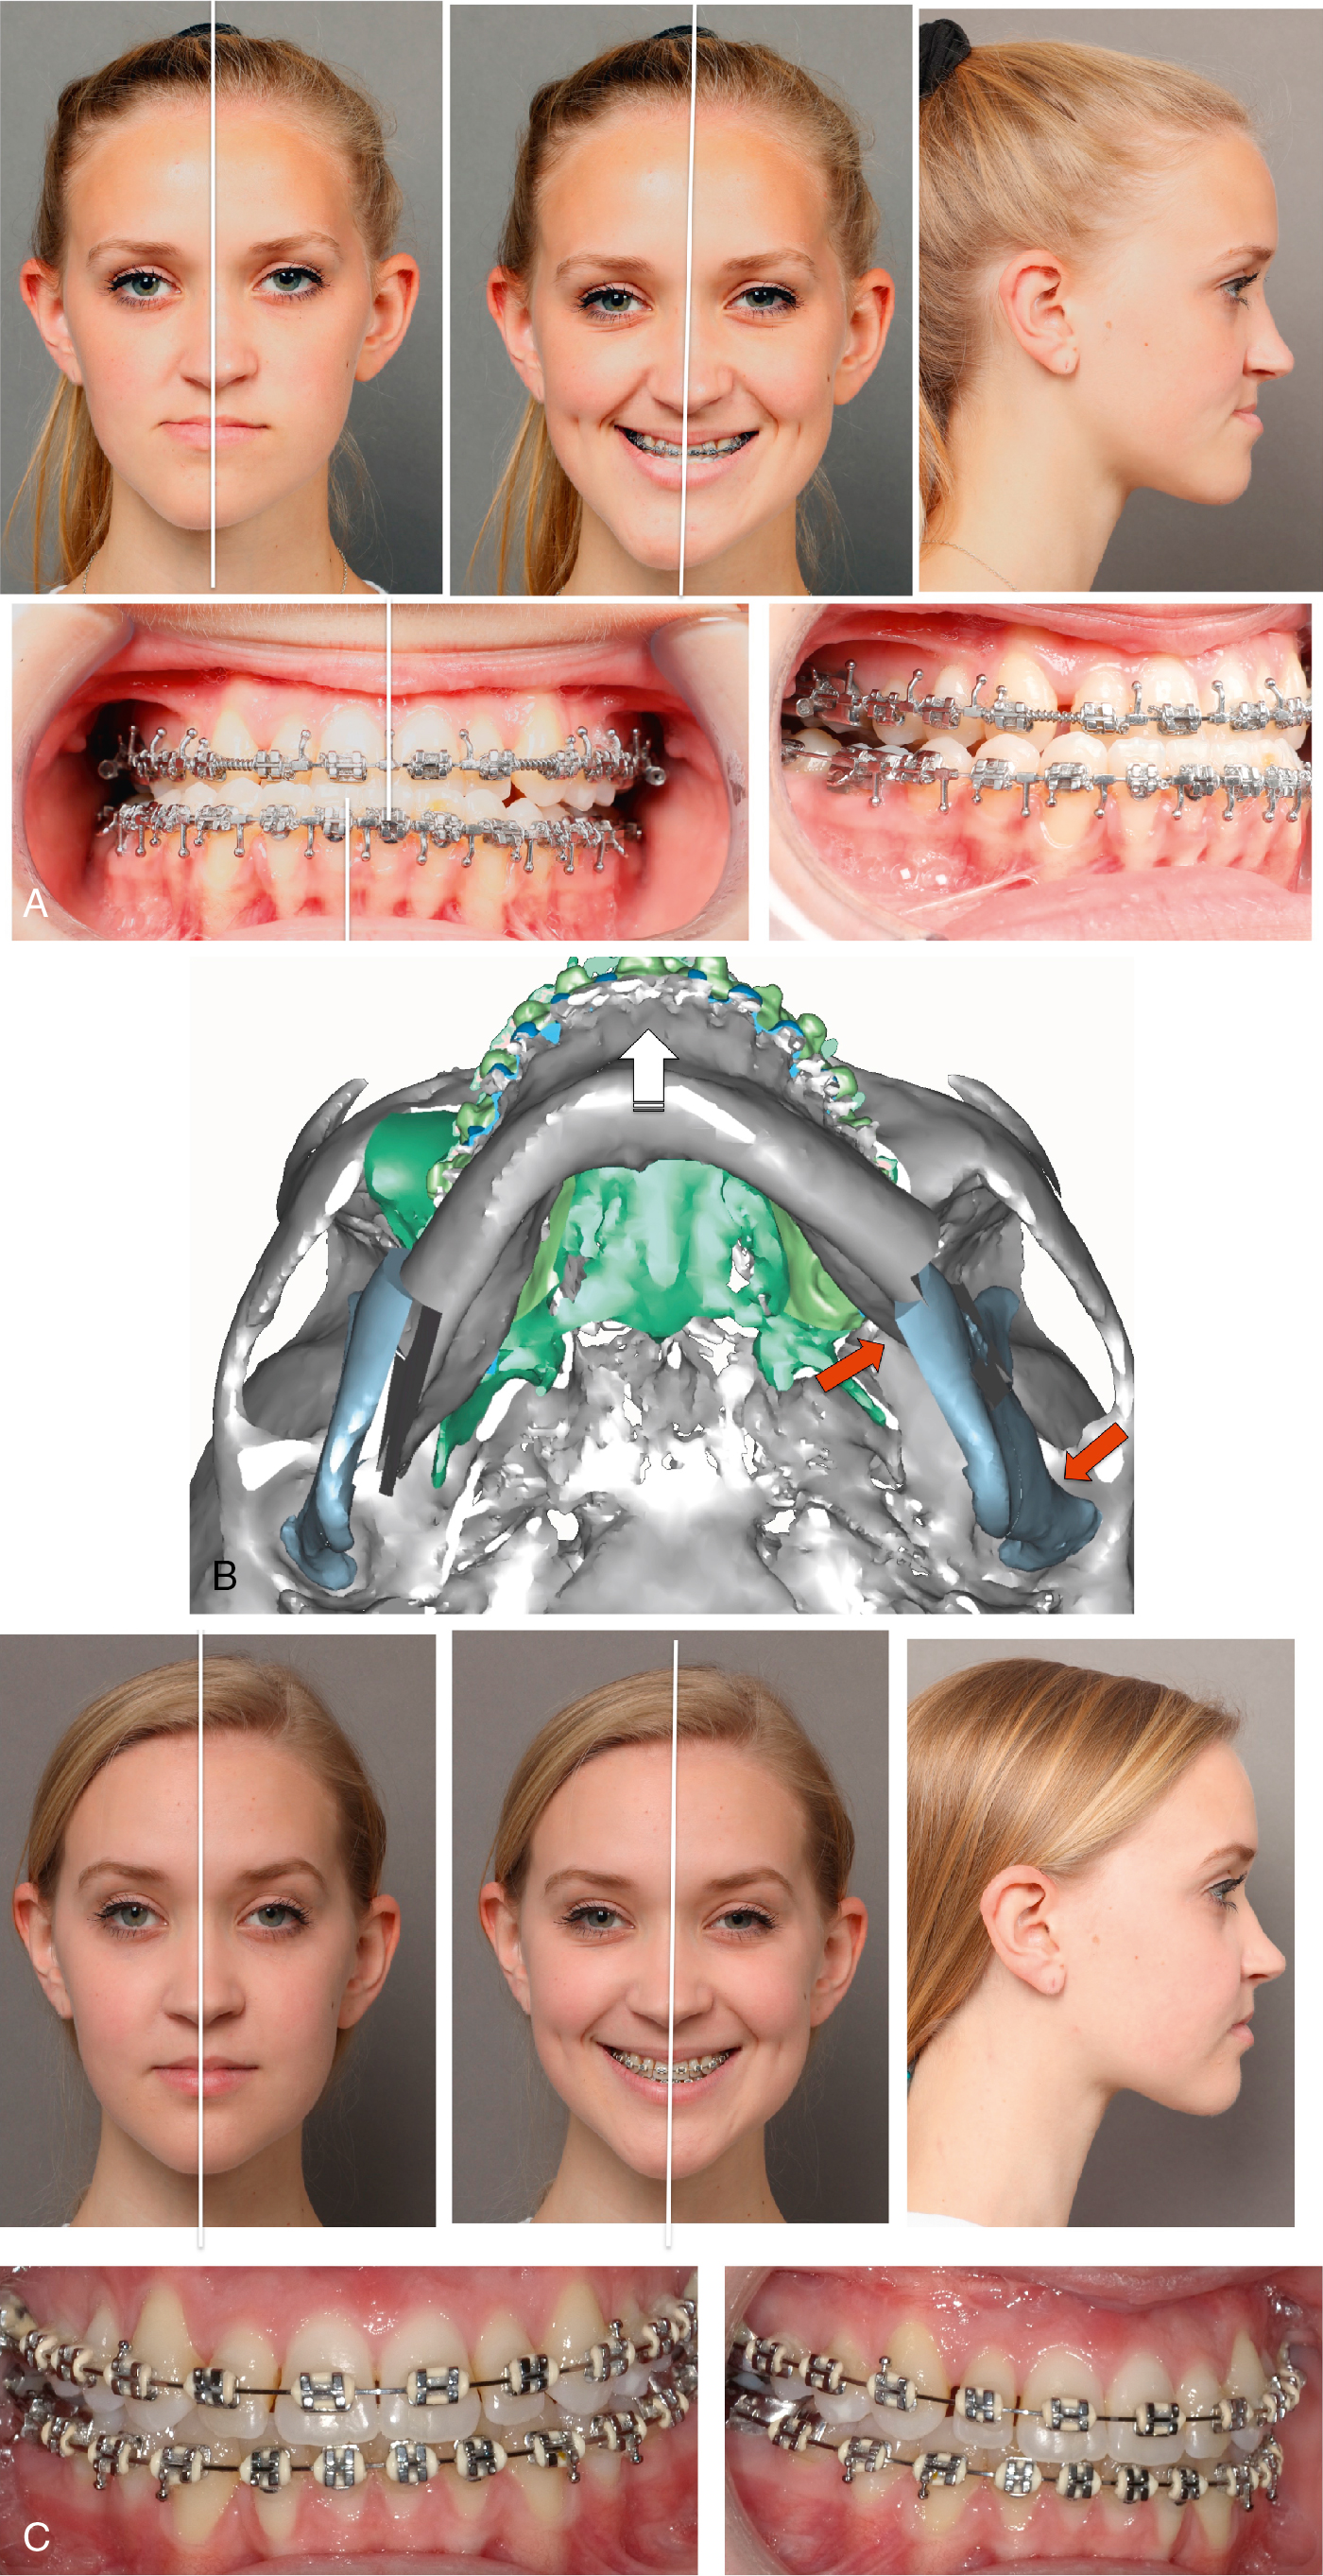

Two-jaw surgery is necessitated when occlusal plane changes are desired to optimize the aesthetic outcome. A classic example is a patient with class II malocclusion with a steep mandibular plane, who would benefit from a significant counterclockwise rotation. When the maxillary and mandibular occlusal planes are divergent, as in patients with apertognathia, posterior maxillary impaction may be insufficient, and mandibular surgery may be required for occlusal stability and aesthetic improvement ( Fig. 22.3 A-C).